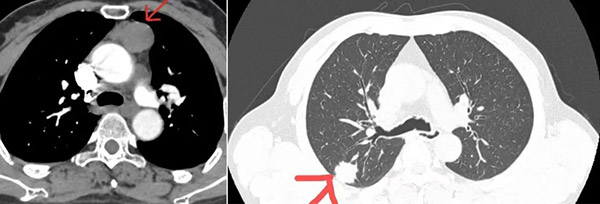

面对年近七旬患者“右肺上叶占位,前纵隔肿物”的检查结果,是依照常规方式行多次手术切除,还是为了减少患者损伤挑战“一次性”解决全部问题?沈阳市第六人民医院胸心外科主任舒健毅然选择了后者。

“看胸部CT检查结果,您右肺上叶占位、前纵隔肿物,考虑是肿瘤,需要手术切除……”听着舒主任的说明,王大哥瞬间觉得天都塌了,一家人陷入深深的焦虑之中。